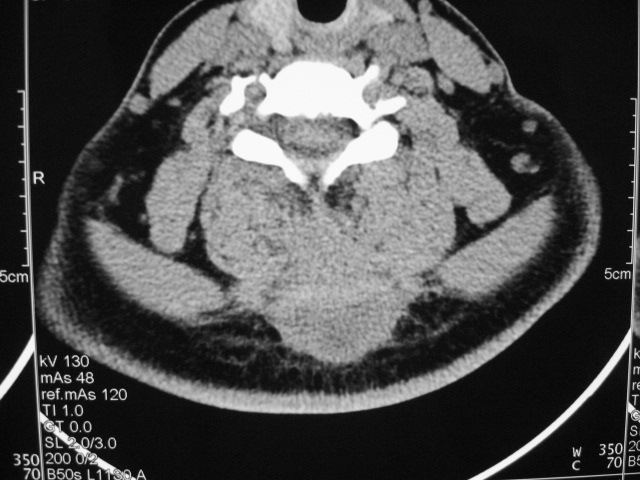

女,46岁,发现颈后区肿块3月余.

颈后软组织肿块,内可见坏死区及点状钙化,邻近颈椎棘突可见破坏,邻近肌间隙模糊,肿块周围脂肪间隙可见索条状影。

考虑:1)感染,结核可能;

2)肿瘤不能排除。